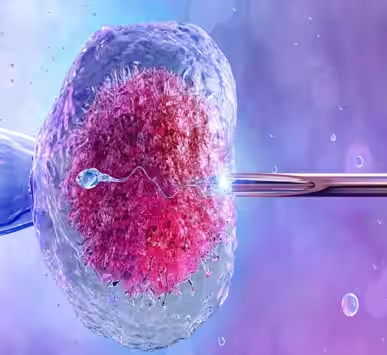

In today’s world, infertility is a common challenge faced by many couples. However, with advancements in medical science, solutions like In-Vitro Fertilization (IVF) have helped numerous families achieve their dream of parenthood

Infertility can be a distressing experience for couples trying to conceive. Fortunately, advanced reproductive technologies like Intracytoplasmic Sperm Injection (ICSI) offer a highly effective solution.

Infertility can be an emotional and challenging journey, but medical advancements have made parenthood possible through the Test Tube Baby process.

Choosing an experienced fertility specialist is one of the most important decisions for couples struggling with conception. A specialist offers advanced diagnosis, modern reproductive solutions, and personalised care to help overcome challenges related to hormonal imbalance, PCOS, endometriosis, sperm disorders, and age-related fertility decline.

With the right guidance and scientifically proven infertility treatment, couples can significantly improve their chances of achieving pregnancy naturally or through assisted reproductive techniques. Many individuals benefit from professional evaluation, lifestyle modification, ovulation tracking, and the right medical support at the right time.

When natural conception becomes difficult, an expert fertility doctor may suggest advanced procedures such as IVF treatment, ICSI, donor programs, or embryo freezing. IVF helps fertilisation occur outside the body under controlled conditions and offers a high success rate for couples experiencing long-term infertility.